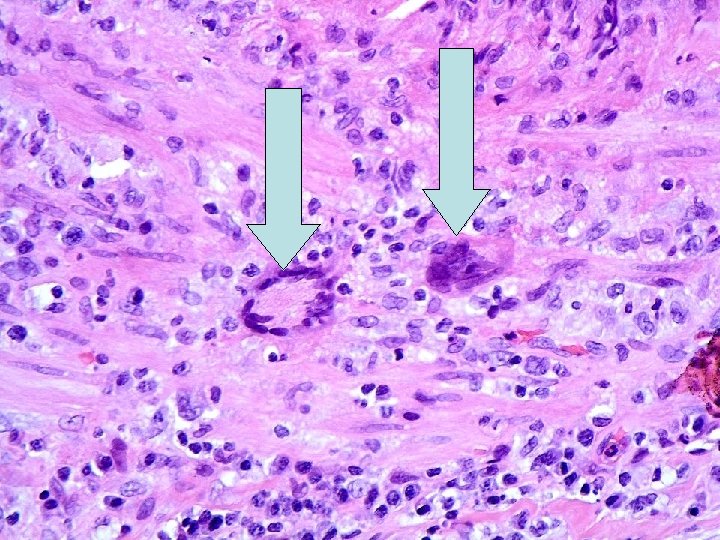

Temporal arteritis

Temporal arteritis Idiopathic, granulomatous vasculitis of large or medium sized elastic arteries. SKIP LESIONS Predilection for superficial temporal artery, but can affect cerebral arteries, carotids, coronary arteries, aorta, renal arteries etc… Pathogenesis-actinically damaged elastic tissue-trigger cell-mediated immune response ? Infection? Histology-with and without giant cells. Adventitial acute and chronic inflammation with involvement of media (muscle layer). Fragmentation of internal elastic lamina. Giant cells at sites of internal elastic lamina rupture (not always). Inflammatory oedema of intima, with stenosis of lumen.

Temporal artery biopsy No evidence base for how long biopsy should be. The longer the better as maximises chances of catching skip lesion. Target biopsy to painful segment-important. During handling in pathology lab- serial sections are cut through the entire specimen (with or without elastin stains), to increase chance of picking up skip lesion.